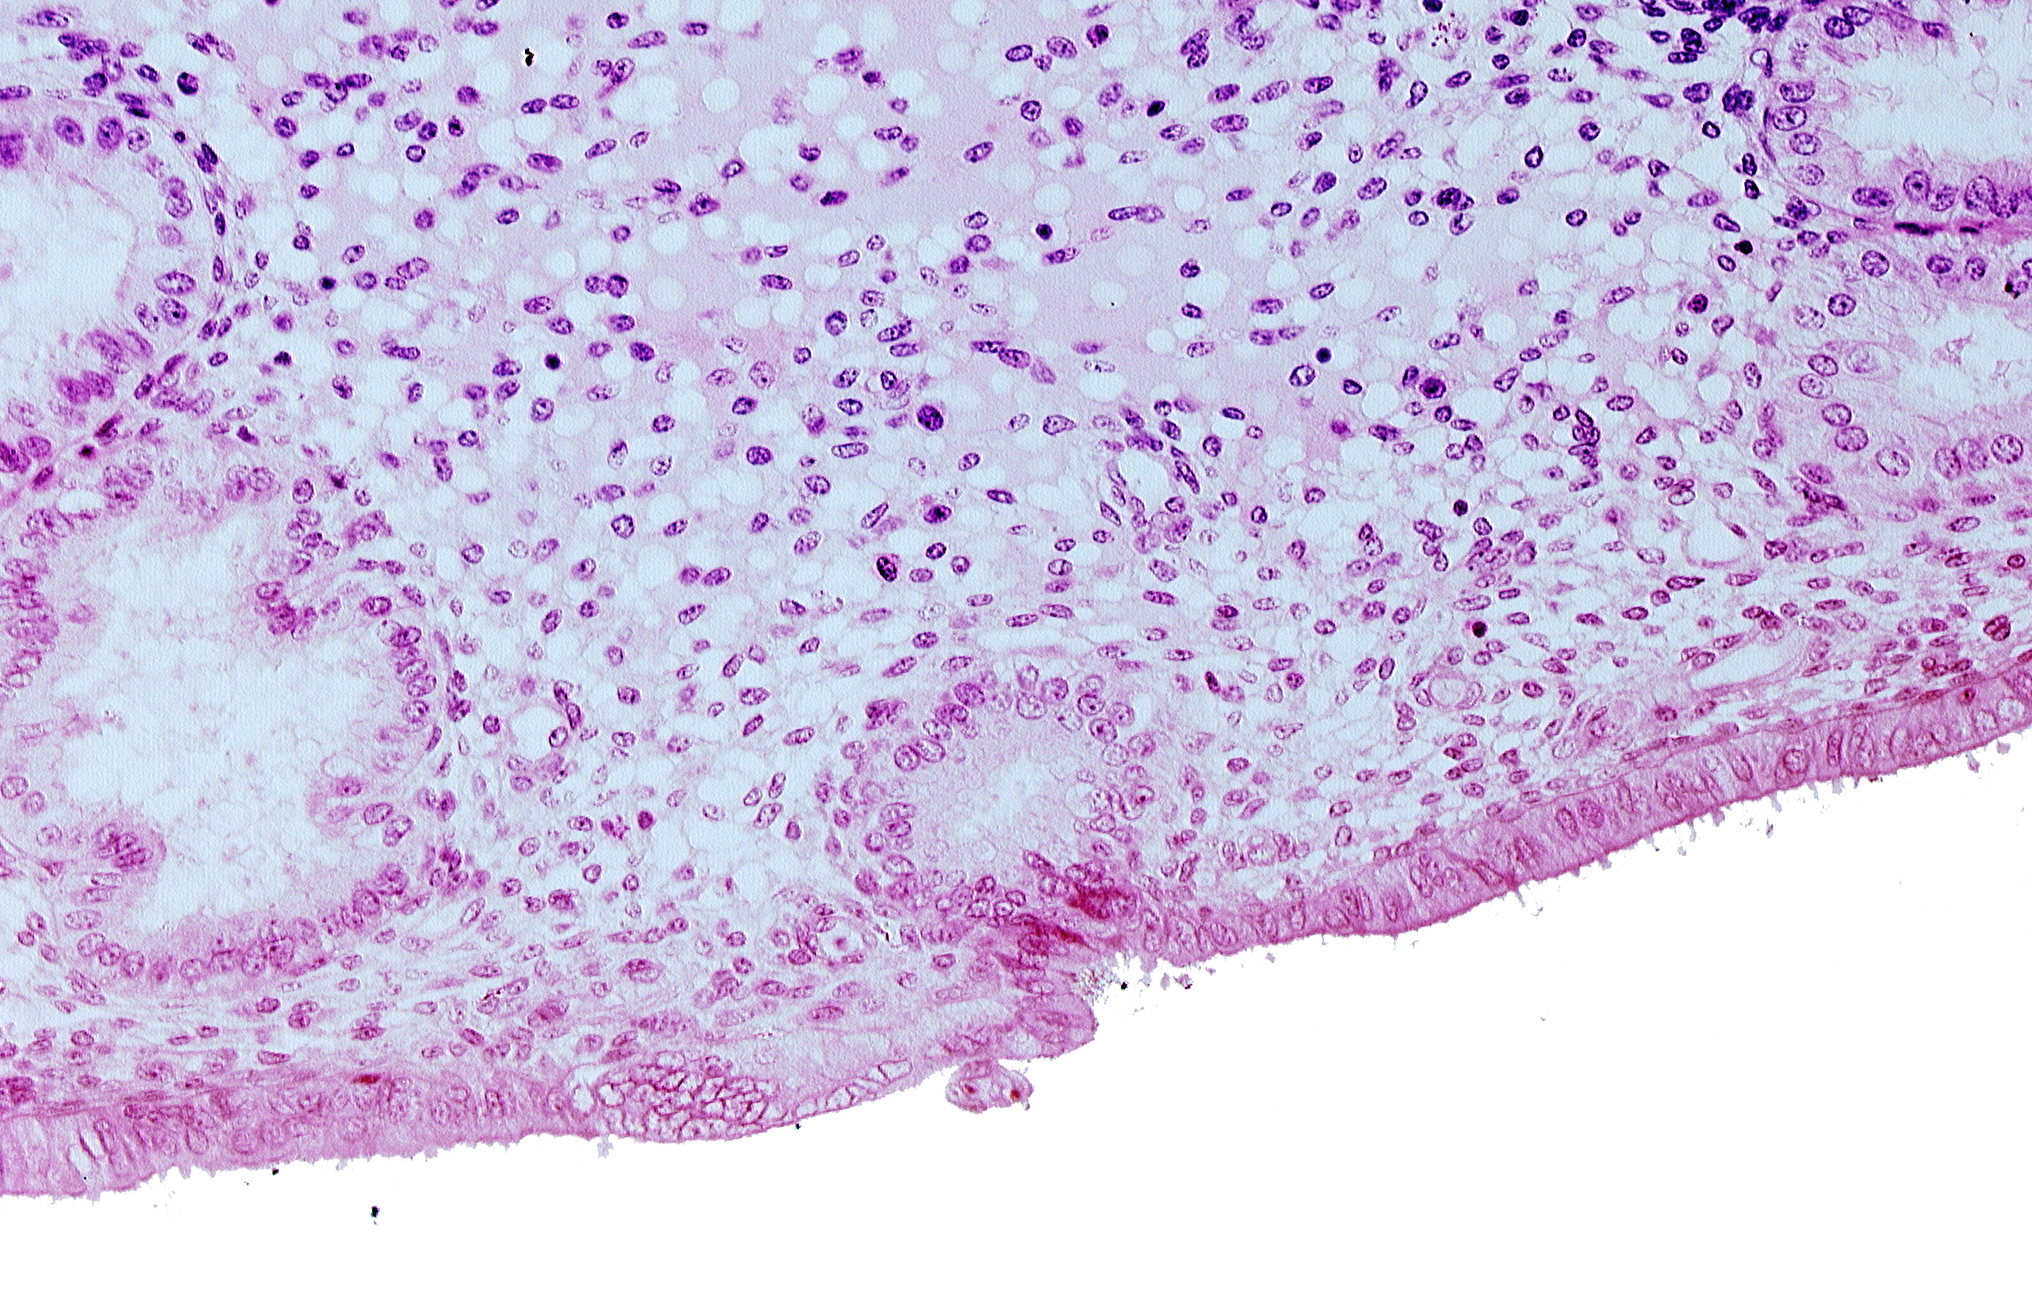

Carnegie Embryo #8020 | Location: 06-06-02

Keywords: disrupted endometrial epithelium, edematous endometrial stroma (decidua), endometrial epithelium, endometrial gland